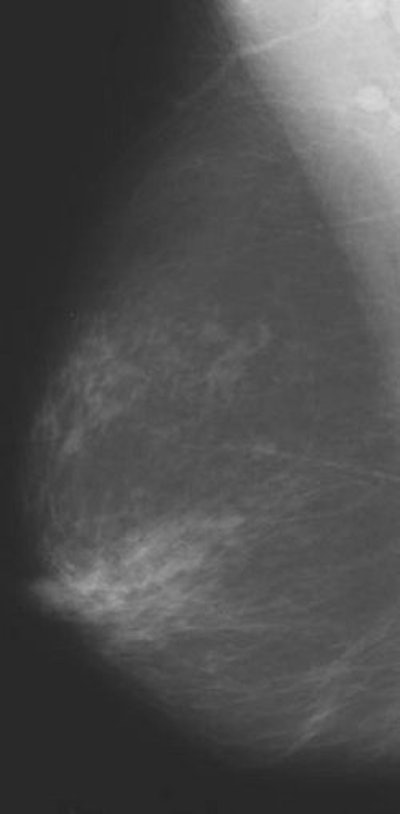

| In this study, one radiologist read baseline mammograms at the time of patient recruitment, and all follow-up mammograms at the end of the study. The second reader read all mammograms at the end, but was unaware of the imaging sequence. |

The results showed there was no difference in estimated percentage density at baseline, mean of 61.8% according to Warren and 61.6% based on Sala's read, or follow-up (58% and 57.4%, respectively). Mammographic density did decrease in both groups, but the difference between treatment and placebo was not statistically significant, the authors wrote.

According to Warren's read, 22% of the women in the isoflavone group changed to a more lucent Wolfe pattern versus 18% of the placebo group. There was no change for 78% and 80%, respectively, and only a 2% change to a denser Wolfe pattern in the placebo group.

According to Sala's read, 15% of those taking isoflavones exhibited a more lucent Wolfe pattern compared to 19% in the placebo group. Eighty-four percent of the women on isoflavones showed no change, as did 80% of the women taking the placebo. Finally, only 2% of both groups showed a denser Wolfe pattern.

The researchers concluded that isoflavones taken as a dietary supplement "did not increase mammographic breast density in women aged 49-65 years, unlike conventional estrogen replacement therapies." In addition, although the study showed a decrease in breast density in both groups, this was most likely because of natural changes over time, they stated. The isoflavones still did not affect density as much as antiestrogens such as tamoxifen.